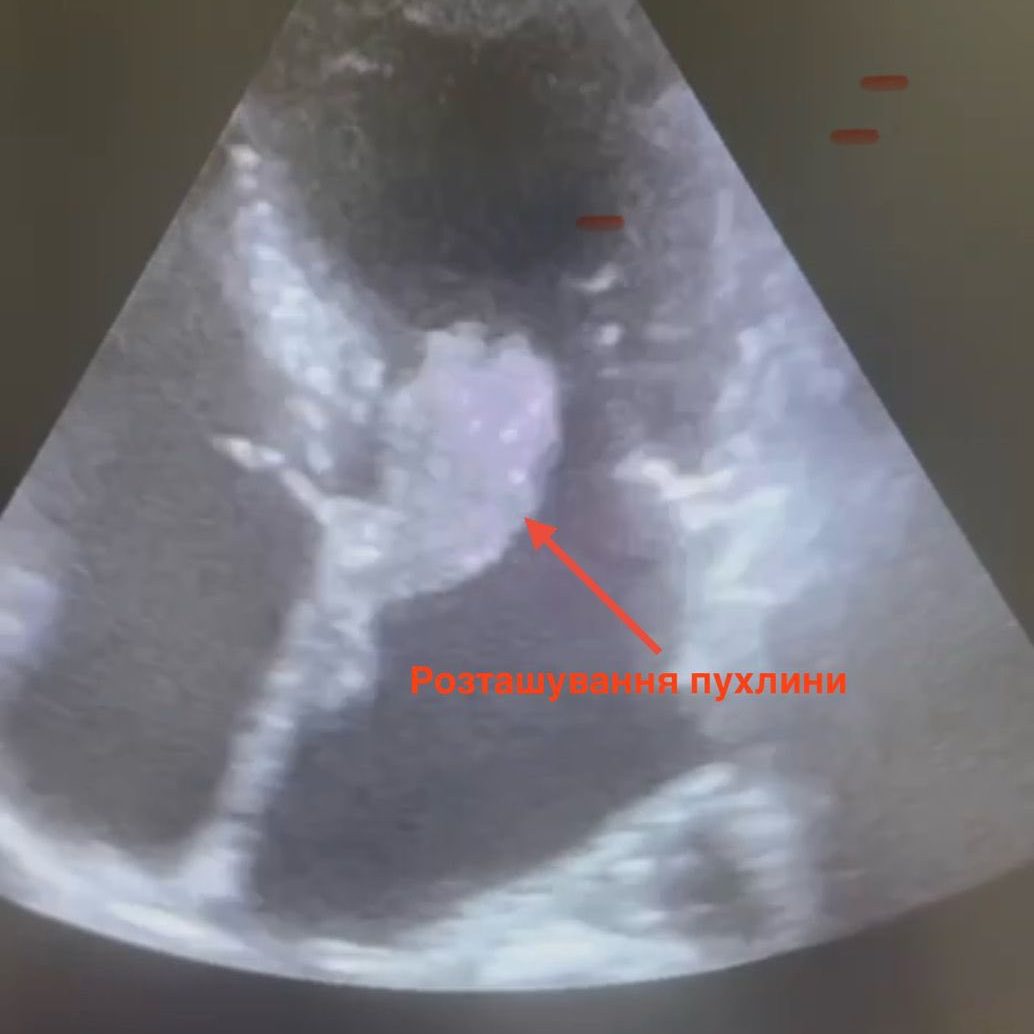

Кардіохірурги Чернівецької обласної клінічної лікарні успішно видалили у пацієнтки міксому лівого передсердя розміром 2,5×5 см — небезпечну пухлину, яка могла будь-якої миті призвести до інфаркту чи інсульту.

Операцію виконали фахівці кардіохірургічного відділення обласної лікарні. За словами лікаря-кардіохірурга Андрія Перепелюка, новоутворення мало желеподібну структуру і не було капсульованим, тож існував ризик його розриву й закупорки судин. Завдяки злагодженій роботі медичної команди вдалося вчасно усунути загрозу і врятувати життя пацієнтці.

Міксома лівого передсердя — одне з найрідкісніших захворювань у кардіохірургії. Вона становить лише 0,25% серед усіх серцевих патологій, але навіть доброякісна пухлина може стати смертельно небезпечною.

Пухлину в серці жінки виявили випадково — під час профілактичного УЗД. Медики наголошують: регулярні обстеження допомагають вчасно виявити небезпечні хвороби і врятувати життя.